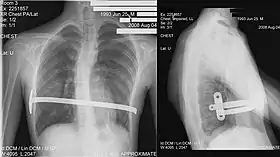

His procedure, widely known as the Nuss procedure, involves slipping in one or more concave steel bars into the chest, underneath the sternum. The bar is flipped to a convex position so as to push outward on the sternum, correcting the deformity. The bar usually stays in the body for about two years, although many surgeons are now moving toward leaving them in for up to five years. When the bones have solidified into place, the bar is removed through outpatient surgery. Although initially designed to be performed in younger children (less than 10 years of age) whose sternum and cartilage is more flexible, there are successful series of Nuss treatment in patients well into their teens and twenties.[56] The Nuss procedure is a two-stage procedure.[56]

Chest x-rays are also useful in the diagnosis. The chest x-ray in pectus excavatum can show an opacity in the right lung area that can be mistaken for an infiltrate (such as that seen with pneumonia).[20] Some studies also suggest that the Haller index can be calculated based on chest x-ray as opposed to CT scanning in individuals who have no limitation in their function.[21]